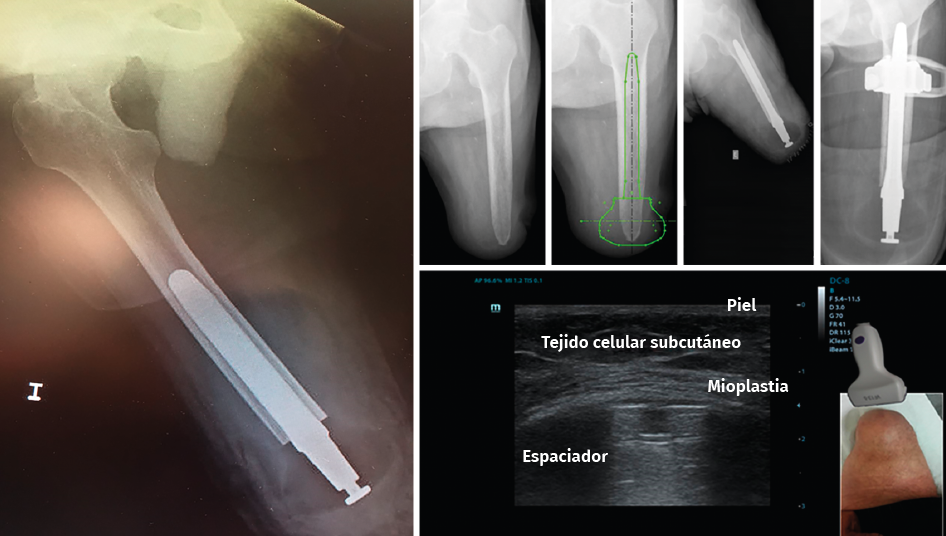

El implante femoral del estudio se compone de 3 piezas (Figura 2). El vástago femoral está fabricado de una aleación de titanio (Ti-6Al-4V) para facilitar el anclaje dentro del canal femoral. La segunda pieza es un espaciador fabricado en polietileno de alta densidad (UHMWPE) que se conecta distalmente con el vástago por mediación de la tercera pieza, un conjunto de tapón de polietileno y tornillo. El espaciador es el que permite el apoyo distal del muñón dentro del encaje.

Figura 2. Componentes del implante endomedular de carga distal Keep Walking®.

Figura 3. Procedimiento quirúrgico del implante Keep Walking®.

Figura 4. Estado final del implante Keep Walking® tras la cirugía y ecografía donde se aprecia la mioplastia distal de los tejidos blandos.

Las longitudes del vástago oscilan entre 120 y 180 mm, el diámetro de 11 a 17 mm y los diámetros de espaciador oscilan entre 54 y 62 mm. Finalmente, se monta el implante definitivo y se inserta impactado a press-fit en el fémur. Los tejidos blandos son suturados realizando una correcta mioplastia alrededor del espaciador (Figuras 4 y 5).